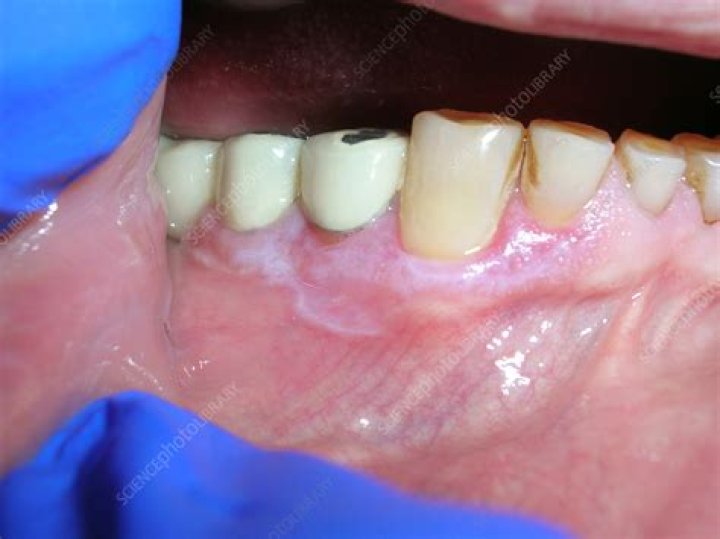

Can amalgam fillings cause lichen planus?

Conclusions: Contact allergyContact allergy Risk factors for allergic contact dermatitis include age, occupation, and history of atopic dermatitis. Overall contact dermatitis is most common in people with red hair and fair skin. Women are more likely to develop contact dermatitis because of the use of jewelry and fragrances. › books › NBK459230

Contact Dermatitis - StatPearls - NCBI Bookshelf

to mercury compounds is important in the pathogenesis of oral lichen planus, especially if there is close contact with amalgam fillings and if no concomitant cutaneous lichen planus is present.

Can mercury fillings cause Oral Lichen Planus?

Conclusions: Contact allergy to mercury compounds is important in the pathogenesis of oral lichen planus, especially if there is close contact with amalgam fillings and if no concomitant cutaneous lichen planus is present.

Metals in close contact with skin and mucous membranes are well-known causes of allergic skin inflammation and mercury is no exception. Among allergic individuals, reactions to mercury or any of the metals in dental amalgam can result in inflammation of the gums, and in red and painful sores and ulcers in the mouth.

It's possible that, in some people, oral lichen planus may be triggered by certain medications, mouth injury, infection or allergy-causing agents such as dental materials. Stress may be involved in symptoms becoming worse or recurring.

What dental materials cause Lichen Planus?

Conclusions Contact allergy to mercury compounds is important in the pathogenesis of oral lichen planus, especially if there is close contact with amalgam fillings and if no concomitant cutaneous lichen planus is present.